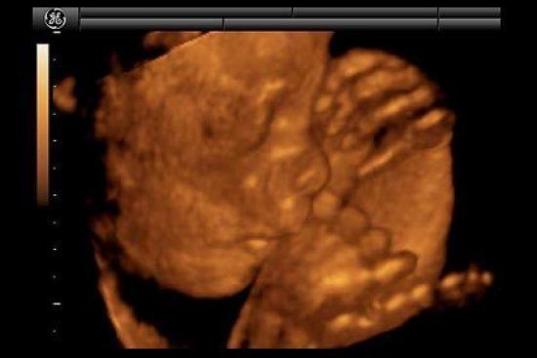

En esta galería puedes ver en fotos como es el desarrollo de un feto de semana en semana:

Desarrollo del feto, en fotos